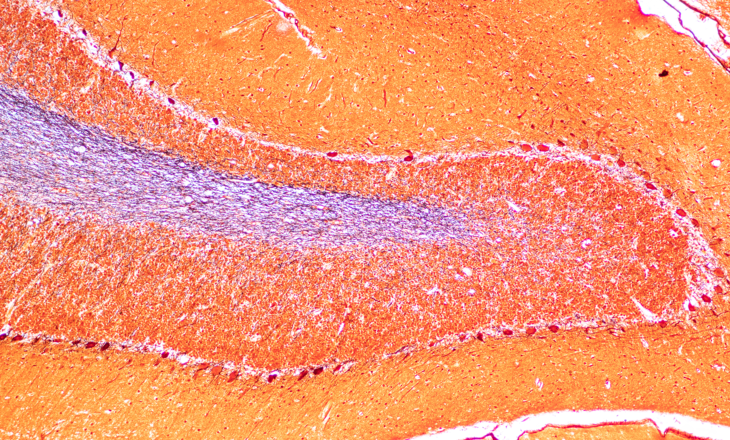

Dr Julie Swillens’ PhD thesis, titled IMPROVING, showed that there is a high degree of variation in diagnostic practice. Palga is committed to reducing this variation by bringing structure to the collection, protection and sharing of pathology data.